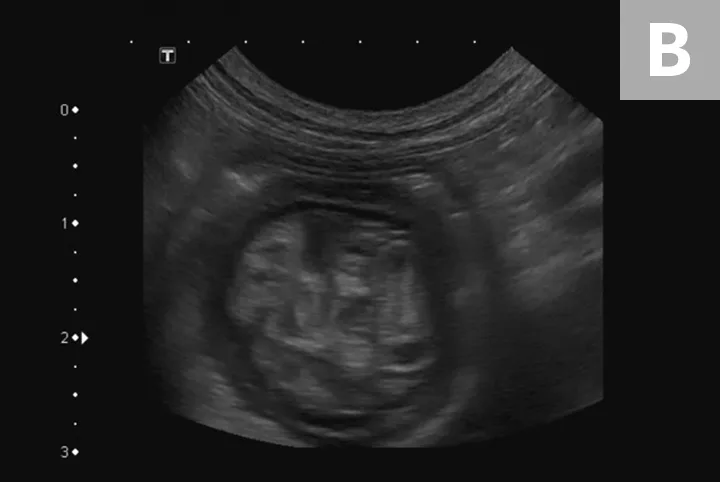

Diagnostic steps include a complete physical examination, abdominal radiography, and abdominal ultrasonography (or a contrast study if ultrasonography equipment is not available). On physical examination, a thickened tubular structure may be palpated in the abdomen, which may be painful for the patient. Abdominal radiographs commonly reveal a fluid- or gas-filled bowel consistent with a mechanical obstruction.2 Abdominal ultrasonography is often the most helpful preoperative diagnostic tool (Figure 1); the finding of multiple hyperechoic and hypoechoic concentric rings in transverse sections, parallel lines in longitudinal sections, or both is diagnostic of intestinal intussusception.4 Abdominal radiography with contrast media (ie, barium) can outline the intussusceptum in the lumen of the intussuscipiens, or the contrast can appear as a ribbon-like structure in the intussusceptum.2

FIGURE 1

Abdominal ultrasound images of a dog with jejuno-jejunal intussusception secondary to an intestinal sarcoma (A), a dog with ileocolic intussusception (B), and a dog with jejuno-jejunal intussusception without an identifiable underlying cause (C)